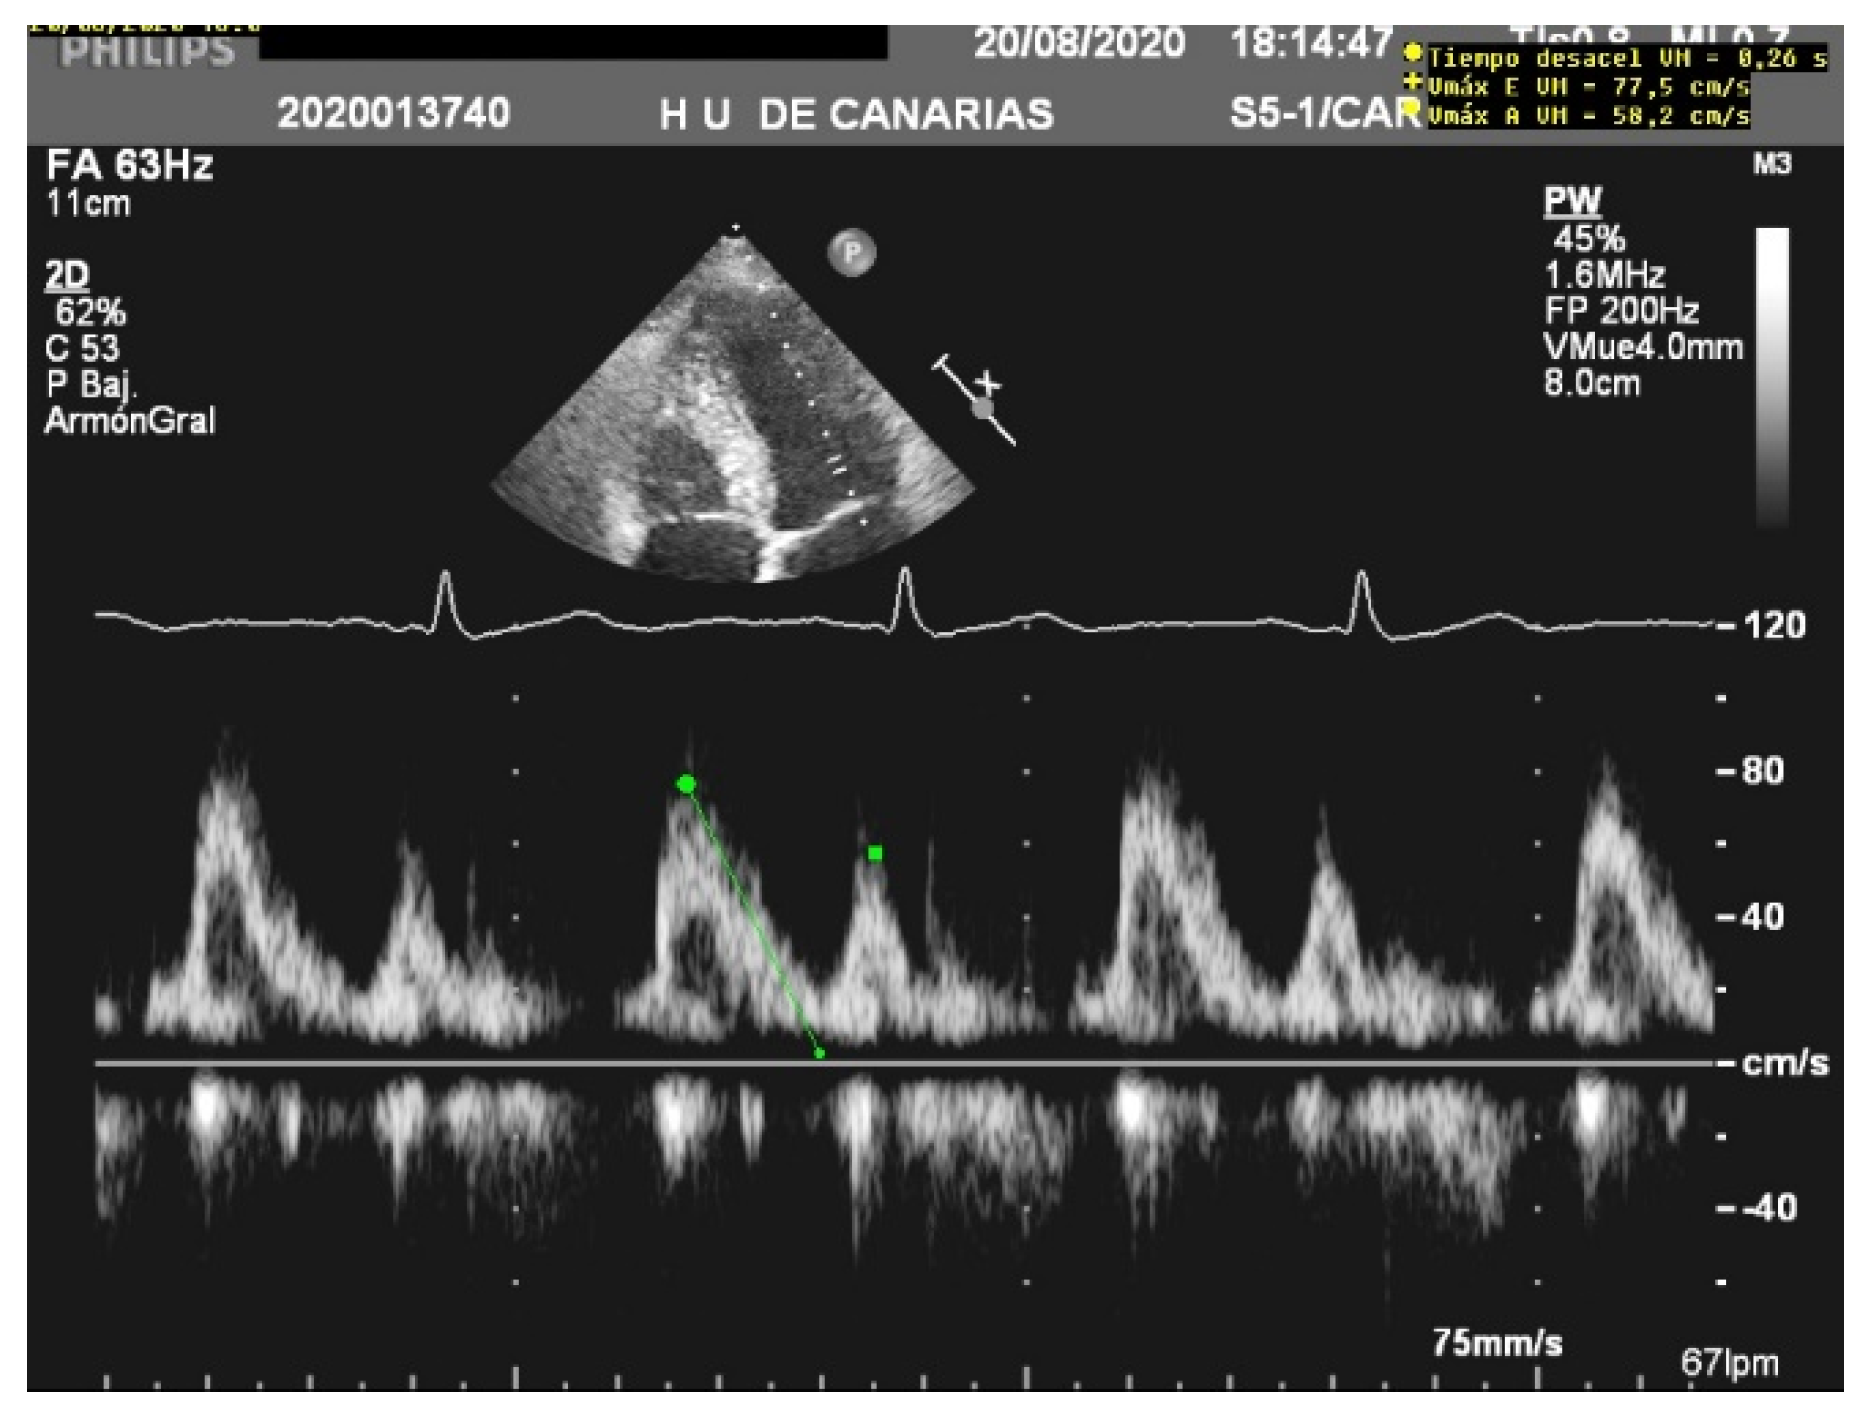

When assessing diastolic function, obtaining an E/e’ mitral ratio higher than 14.5 is associated with higher rates of weaning failure, even in atrial fibrillation [13,19,20], as are E waves higher than 0.87 m/s [13,21] (Figure 1). However, this method is less reliable in acute decompensated heart failure and left ventricles with larger volumes, where significant mitral regurgitation can lead to underestimation, as well as in resynchronization therapy and wide QRS and the subsequent change in septal e’ due to its abnormal motion [22,23].

Figure 1.

E wave height, deceleration time, and A wave. Normal filling pattern.

The E/A ratio is not useful in critically ill situations, as this parameter frequently suffers from a “pseudonormalization” issue [13], with a difficult quantitative interpretation. However, the presence of a “pseudonormal” or restrictive pattern is related to higher rates of weaning failure [20] (Figure 2). A reduction in the E wave deceleration time below 175 ms, in addition to other parameters which can reflect diastolic impairment, such as raised left-atrial pressure indicated by interatrial septal fixed rightward curvature and left-atrial area larger than 25 cm2, is a significant predictor of extubation failure [21]. Moreover, failure is significantly associated with a higher pulmonary capillary edge pressure and elevated pulmonary venous systolic filling [20].